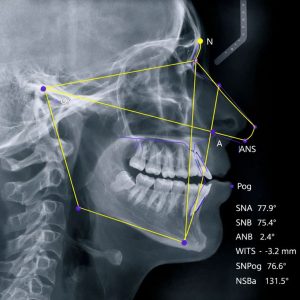

- U ortodonciji za planiranje terapije i praćenje rezultata

- U protetici i implantologiji za precizno planiranje rada